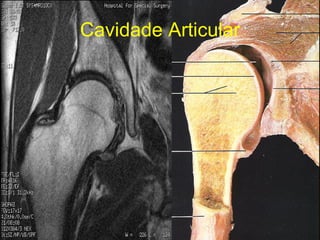

Cavidade Articular Não tem nervos ou vasos sanguíneos É nutrida pelo líquido sinovial que cobre sua superfície livre, provindo dos capilares na membrana sinovial

Cavidade Articular

Cavidade Articular Nãotem nervos ou vasos sanguíneos É nutrida pelo líquido sinovial que cobre sua superfície livre, provindo dos capilares na membrana sinovial